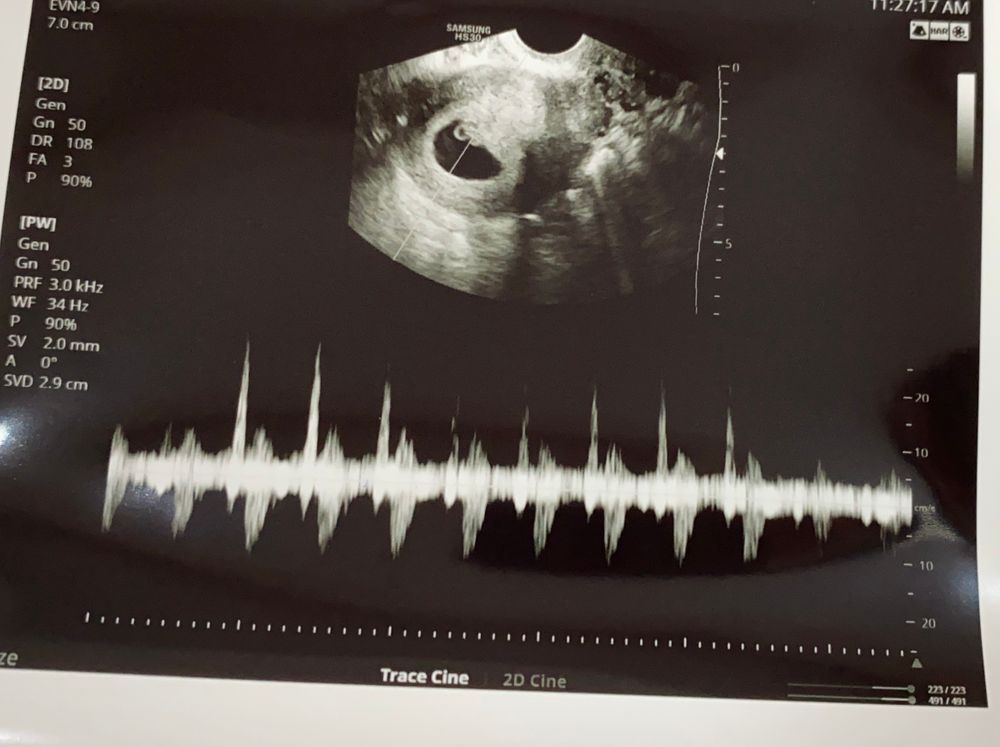

6 недель или 29дпп

Я БЕРЕМЕННА !Всем привет сегодня была на узи , сб+